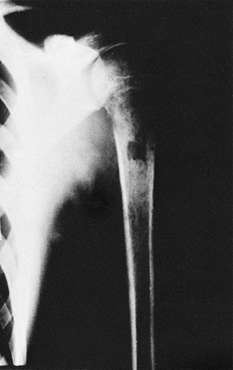

demonstrated that metaphyseal vessels transverse the proximal femoral

epiphysis can be severely damaged from the infection (Fig. 176.1). The vessels that cross the physis in the neonate progressively disappear beginning at 8 months of age (42).

![]() |

Figure 176.1. A: Two-month-old infant with osteomyelitis in the right femur. Note the soft-tissue swelling. B: Three months later, there is widening of the metaphysis with cupping as well as resorption of the ossified epiphysis. C: Seven months later, the femur was already shorter than the opposite femur.